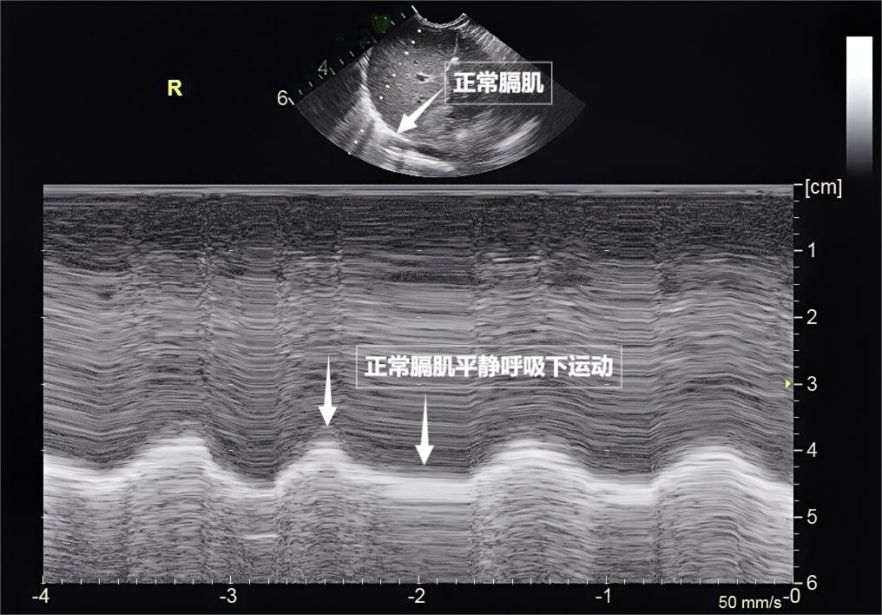

第三景:“呼吸的动力泵”的协同作战——呼吸肌肉

呼吸看似简单,实则是多组肌肉精密配合的“团体操”。肺部超声不仅能观察肺的形态,更能通过实时动态影像,“捕捉”这些呼吸肌的活动状态,为评估呼吸功能提供独特视角。膈肌是呼吸肌的“总指挥”,位于胸腔与腹腔之间。平静呼吸时,膈肌收缩下沉,胸腔容积扩大,空气自然吸入;舒张时,膈肌回升,肺部弹性回缩完成呼气。超声下可见膈肌呈光滑弧形,随呼吸规律上下移动( 见下图 )。肋间外肌则是“肋间隙的升降机”,收缩时上提肋骨,扩大胸腔前后径,辅助吸气。这对“黄金搭档”承担了日常呼吸70%以上的工作量,是维持呼吸的“主力军”。

图为正常膈肌超声表现